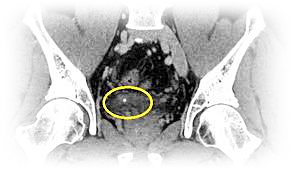

이러한 결석은 보통 신장에서 발생합니다.

신장, 요도, 방광, 요도 등에 있습니다

문제를 일으키고 있어요.